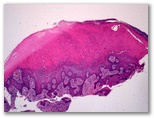

Granuloma piogenico

Diagnostico